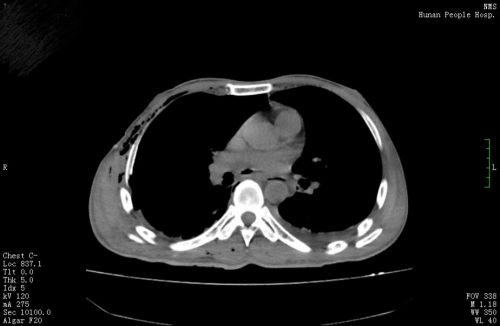

术前,心脏被挤压至左侧胸腔内。

“这个畸胎瘤长在右侧胸腔,体积巨大,压迫右肺、心脏等脏器,手术难度和风险极大”,心胸外科周文武主任医师团队对患者病情进行认真讨论、评估,并做好充足准备后,于83日为其施行“右侧胸腔占位切除+左心房成形术”。